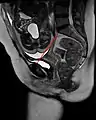

Conjugata vera as measured on sagittal MRI